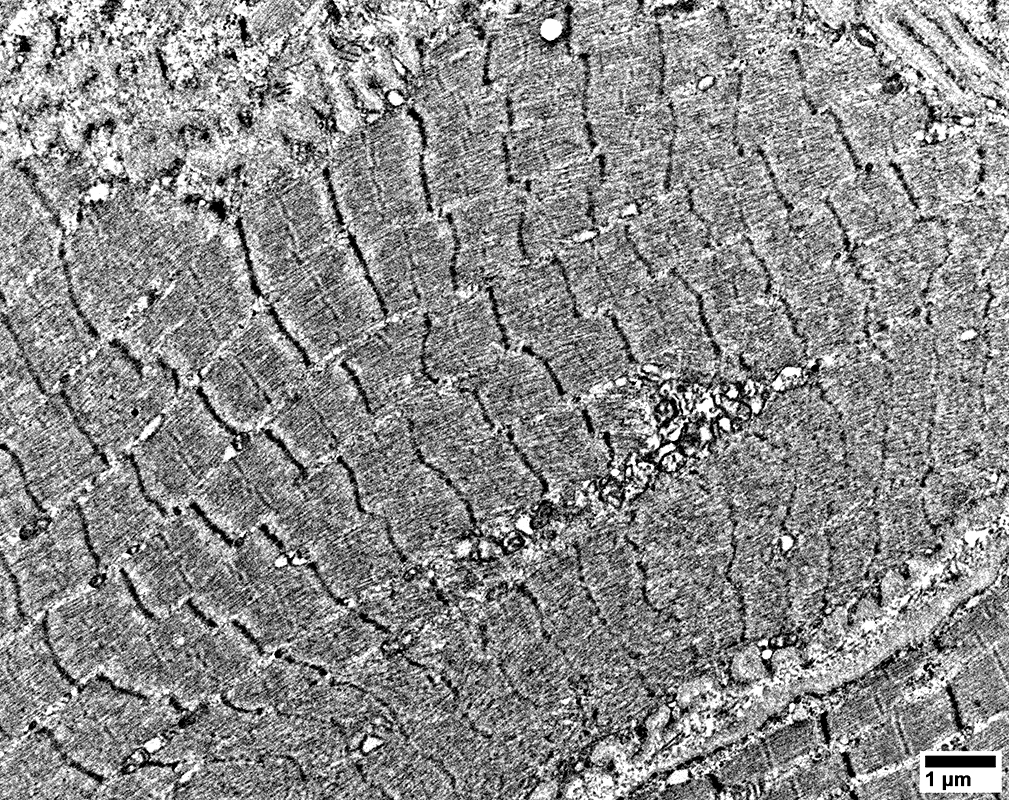

MELAS: Mitochondrial Ultrastructure

From: R Schmidt

Mitochondrial proliferation between sarcomeres

Muscle fiber basement membrane

Thick

Undulating

Mitochondrial proliferation & enlargement: Beneath muscle fiber surface